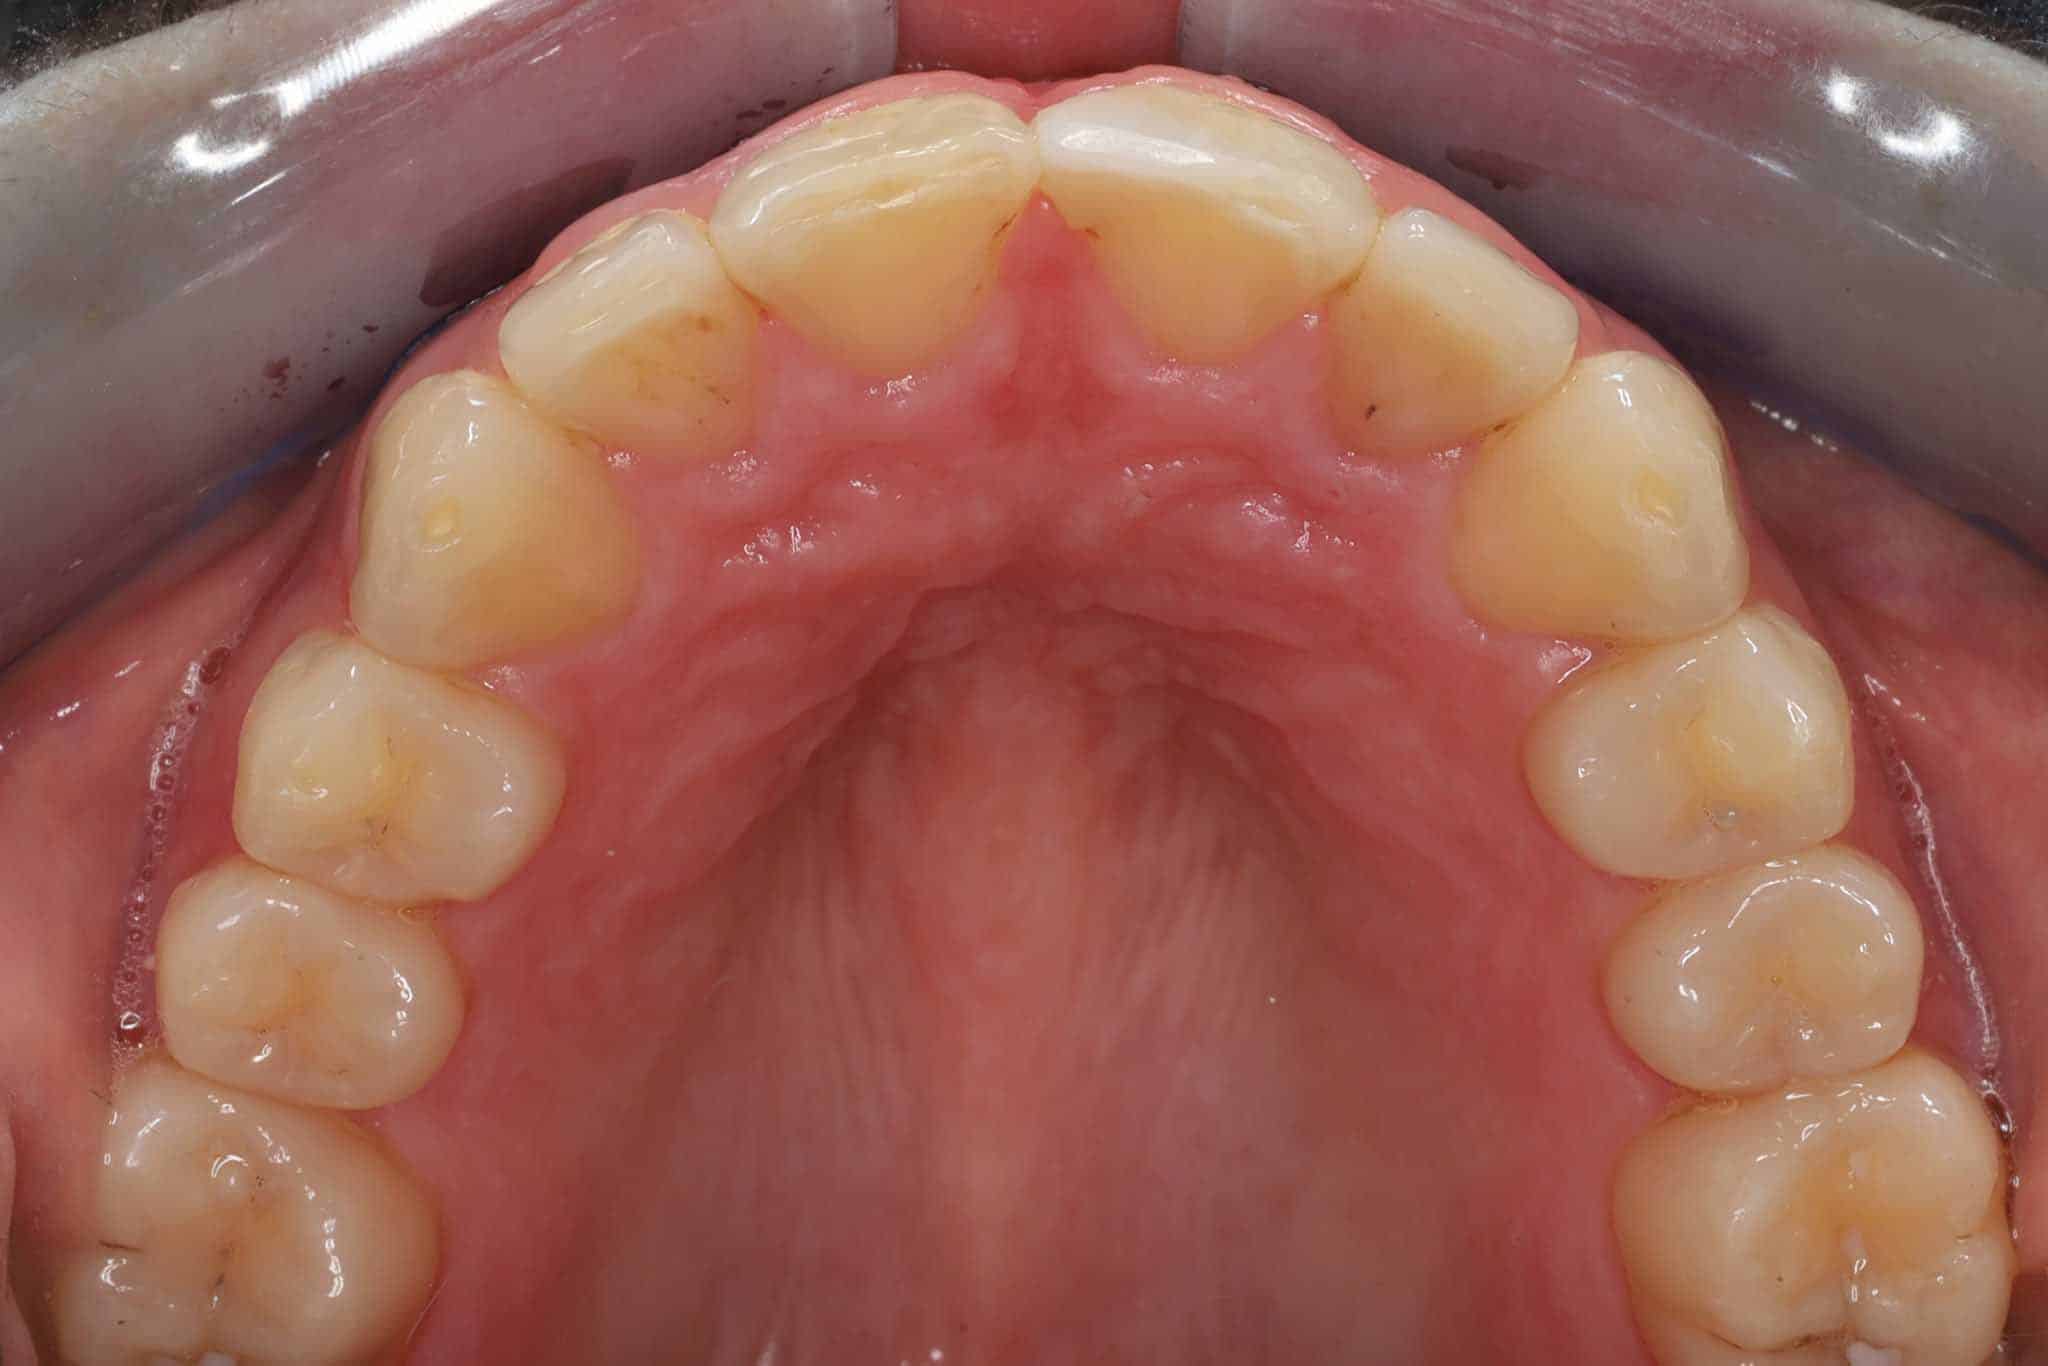

Før- og etterbilder – Resultater fra retainerbehandling

Bildet viser en retainertråd i metall festet til bakpå overkjeve fortennene.

Bildet viser retainertråd festet bakpå overkjevens fortenner.